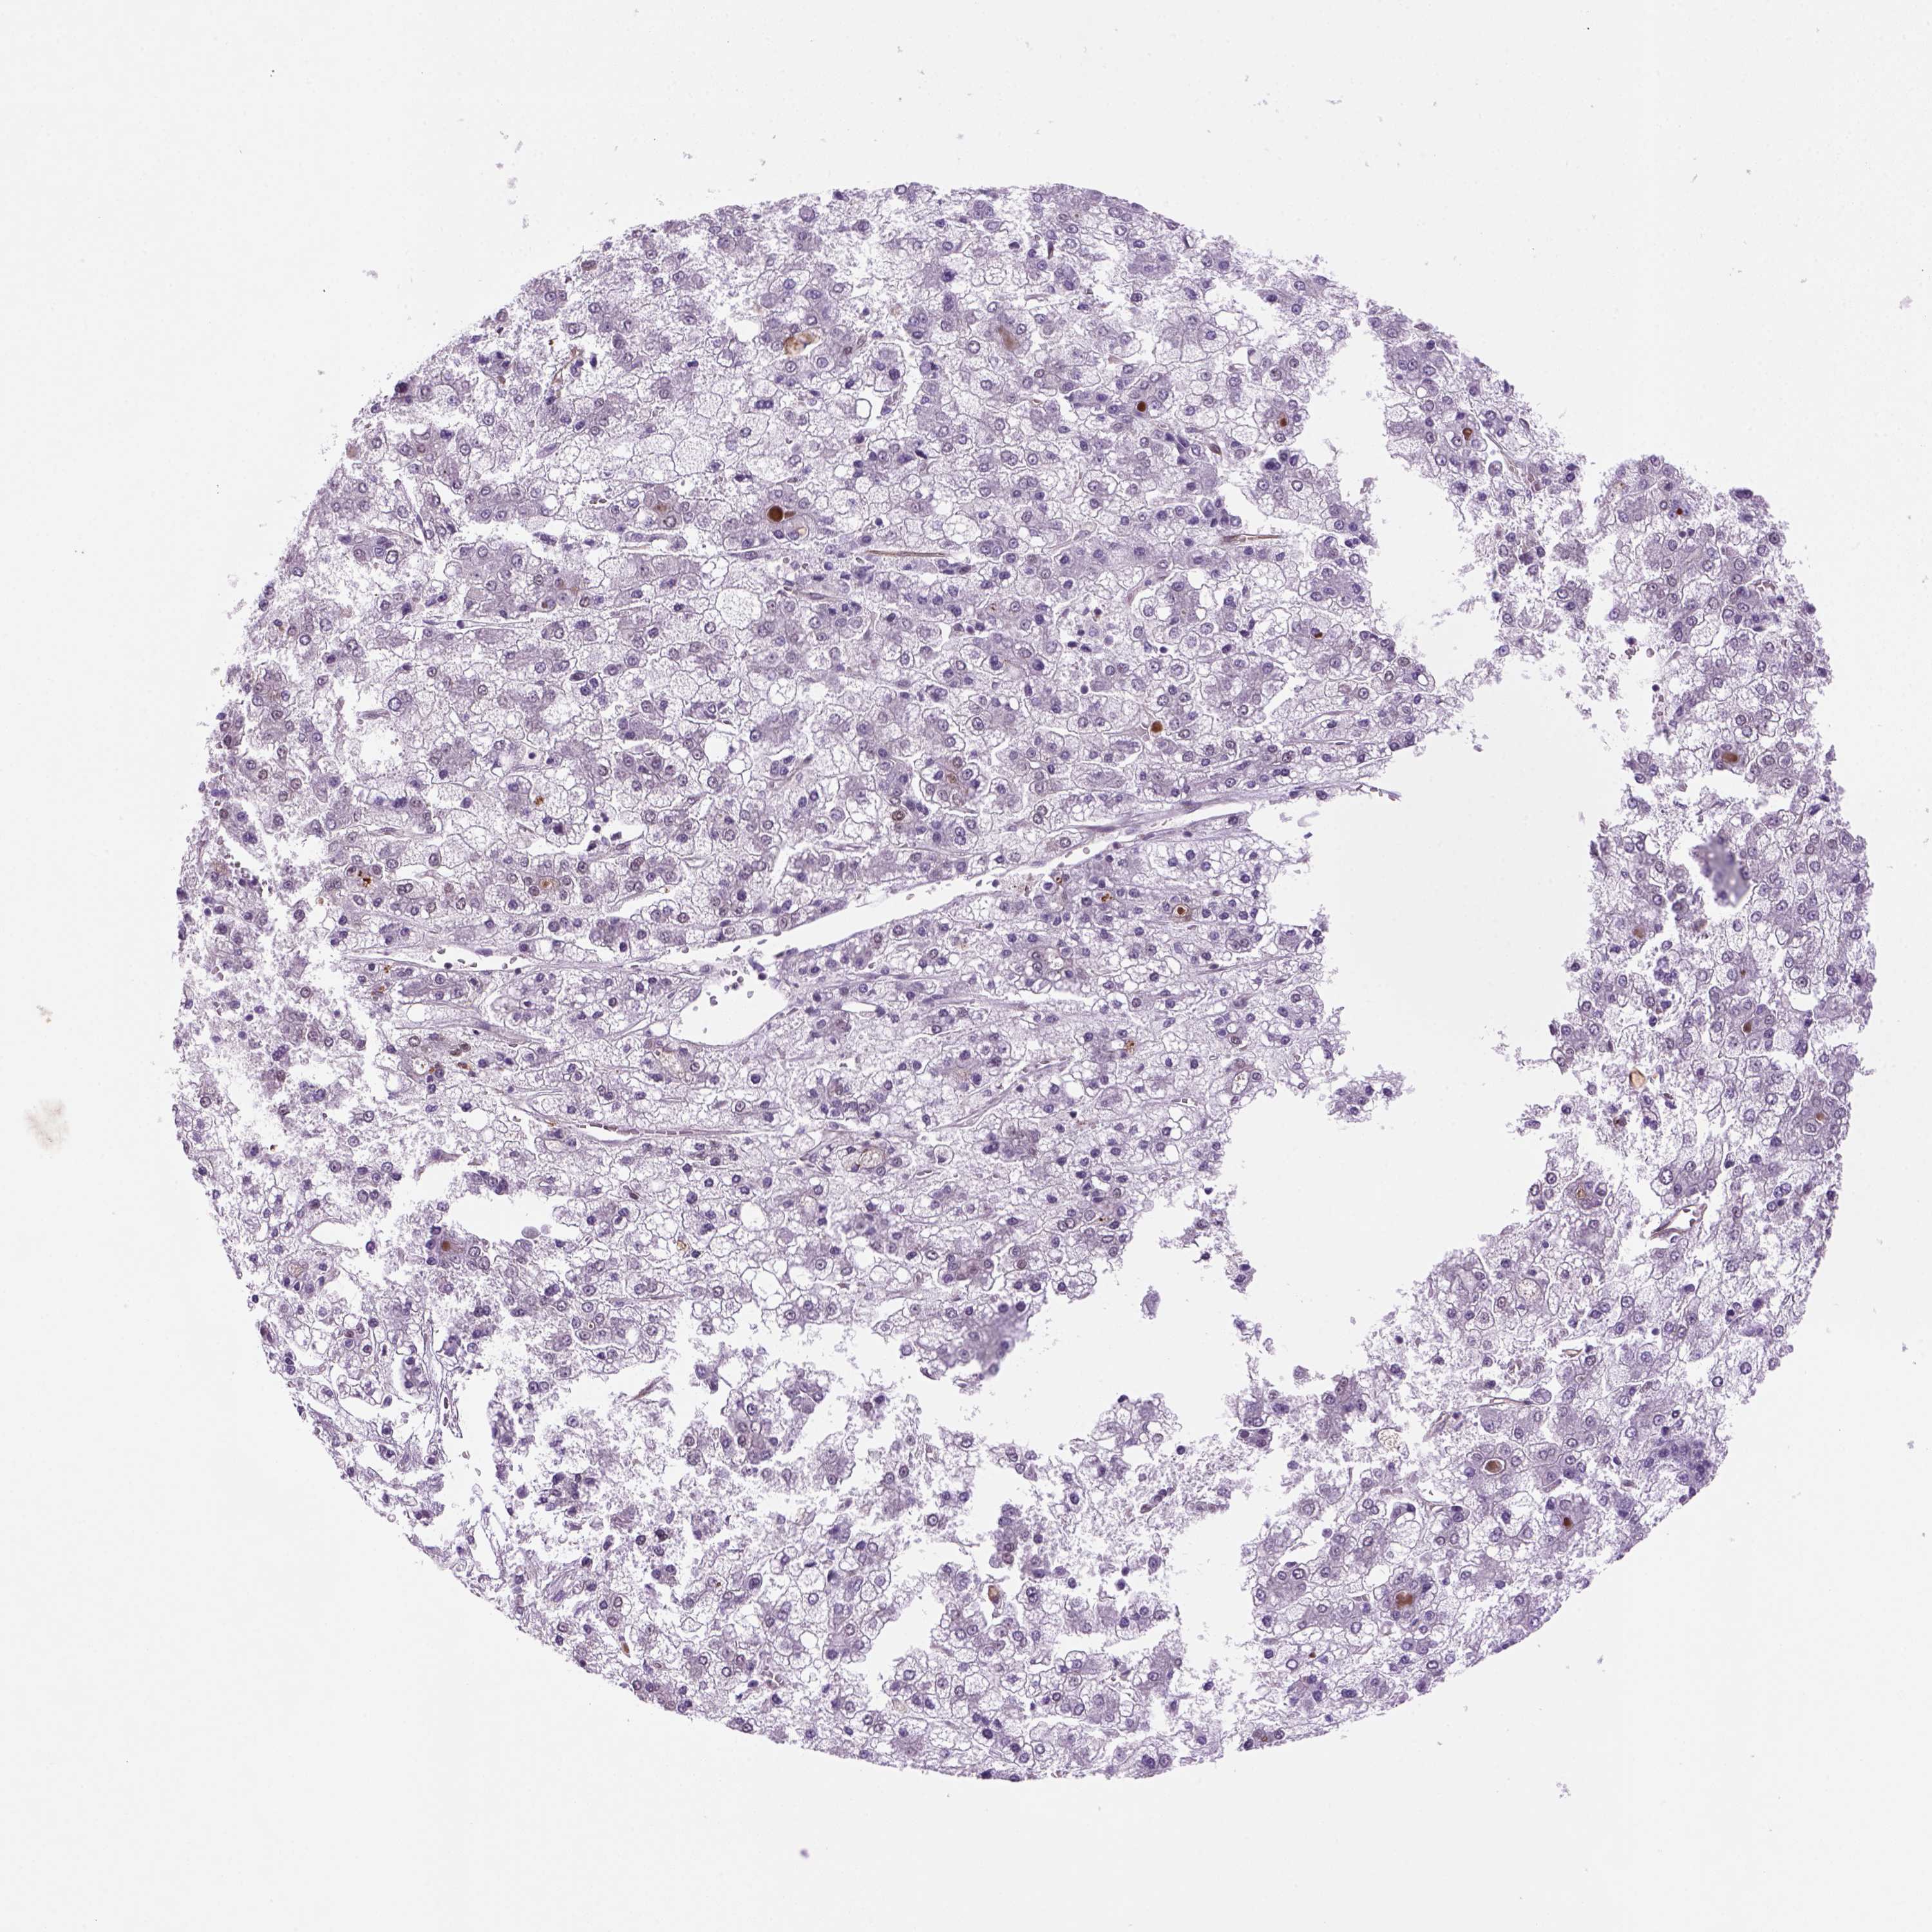

LIVER CANCER - Protein expressioni

A mouse-over function shows sample information and annotation data. Click on an image to view it in a full screen mode. Samples can be filtered based on level of antibody staining by selecting one or several of the following categories: high, medium, low and not detected. The assay and annotation is described here.

Note that samples used for immunohistochemistry by the Human Protein Atlas do not correspond to samples in the TCGA dataset.

Antibody stainingi

Antibody staining in the annotated cell types in the current human tissue is reported as not detected, low, medium, or high, based on conventional immunohistochemistry profiling in selected tissues. This score is based on the combination of the staining intensity and fraction of stained cells.

Each image is clickable and will lead to virtual microscopy that enables deeper exploration of all samples and also displays staining intensity scores, fraction scores and subcellular localization as well as patient and tissue information for each sample.

Antibody HPA069497

Antibody CAB002786

Antibody CAB069881

Staining

High

Medium

Low

Not detected

Intensity

Strong

Moderate

Weak

Negative

Quantity

>75%

75%-25%

<25%

None

Location

Nuclear

Cytoplasmic/membranous

Cytoplasmic/membranous,nuclear

Carcinoma, Hepatocellular, NOS

Cholangiocarcinoma